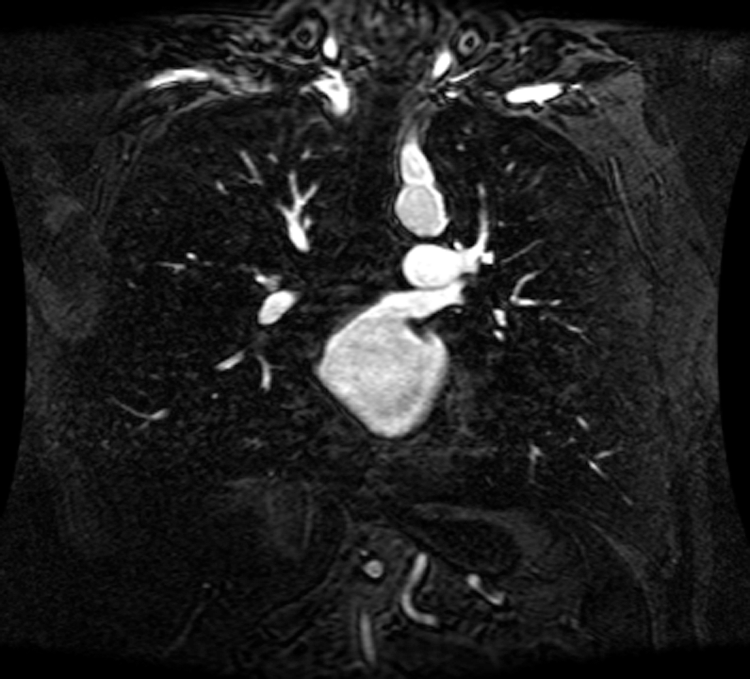

An intelligent-MRI VLC has been implemented for MRI image transmission using VLC and RF interference is eliminated. The proposed intelligent-MRI VLC system is experimentally analyzed using MRI images of different sizes i.e., 100, 115, and 120 KB respectively. These MRI images of the chest are downloaded from a medical database physionet.org. The downloaded MRI images are of T1 weighted type, which has grey matter darker than white matter was used for the proposed work. Images are acquired using Image Acquisition (IMAQ) in LabVIEW and transmitted using visible light in an indoor environment. The downloaded MRI images of various sizes are shown in Figs. 13–15.

Figure 15: 120 KB MRI image